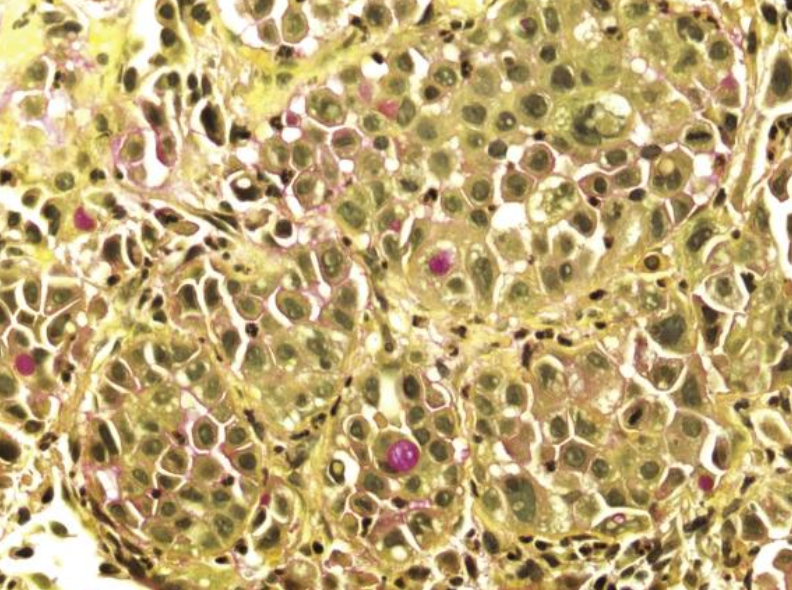

<p>Carcinoma de células gigantes</p>

Carcinoma de células gigantes